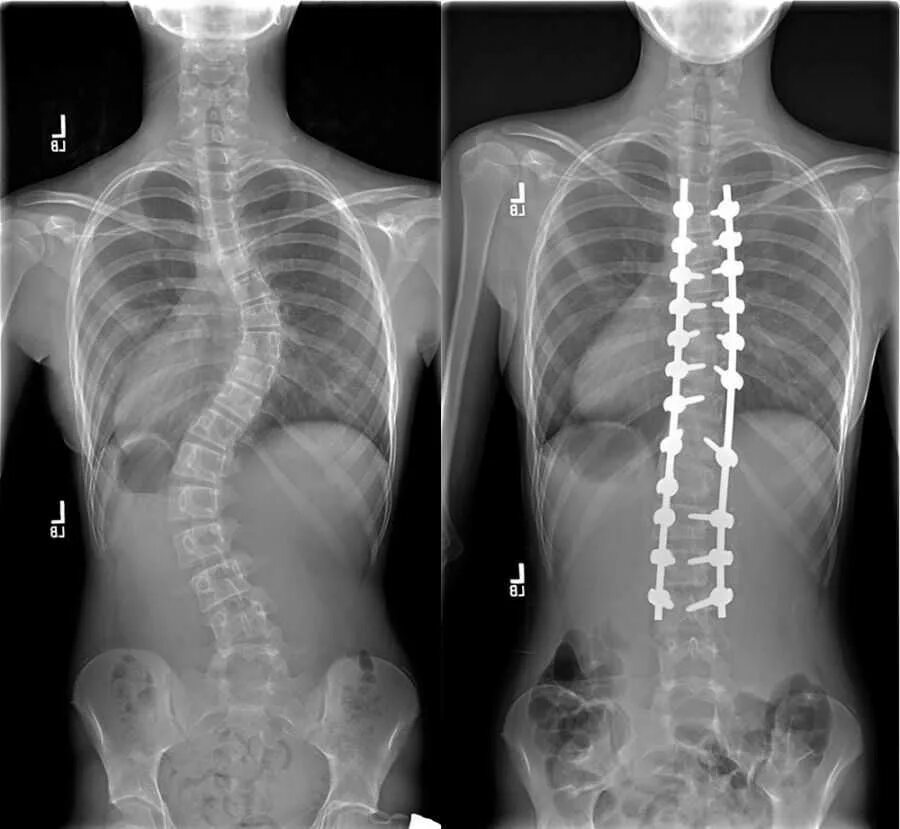

Сколиоз хирургия